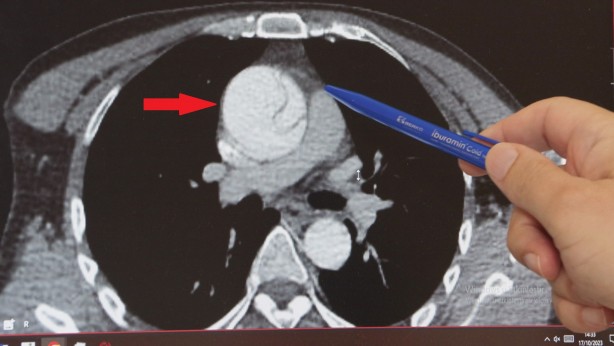

İSTANBUL'da 41 yaşındaki Mustafa Turan, göğsünden karnına doğru aniden başlayan şiddetli bir ağrı ile acile kaldırıldı. Tetkikleri normal çıktı, mide ağrısı sanılıp eve gönderildi. Sonraki 24 saat boyunca ağrısı hiç azalmadı, gece 02:00 sularında Göztepe Süleyman Yalçın Şehir Hastanesi aciline gitti ve nöbetçi doktorun dikkati sayesinde yapılan ileri tetkiklerle, aort damarında anevrizmaya (baloncuk) bağlı yırtık olduğu tespit edildi. Acilen ameliyata alınan Turan, şans eseri ölümden döndü. Kalp Damar Cerrahisi Klinik Şefi Prof. Dr. Ebuzer Aydın, risk grubunda olanların düzenli kontrol yaptırması gerektiğini söyledi ve "Yırtığa bağlı acil ameliyatla, planlı ameliyatlar arasında ölüm riski açısından 4-5 kat fark var" dedi.